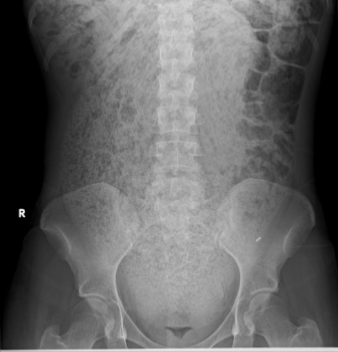

What is this and what type of scan

Bowel wall inflammation/toxic mega colon, abx